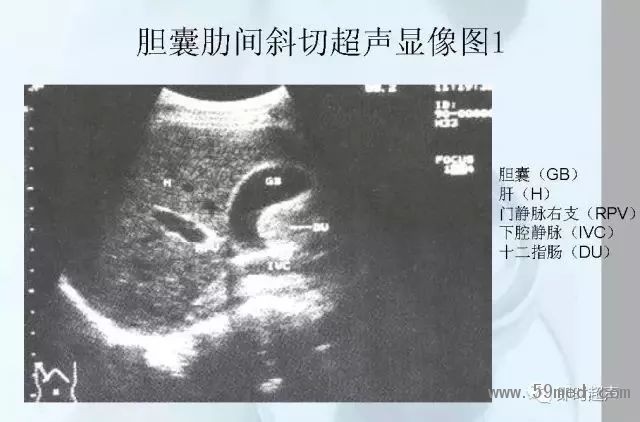

![]() ![]() ![]() ![]() ![]() ![]() ![]() ![]() ![]() ![]() ![]() ![]() ![]() ![]() ![]() ![]() ![]() ![]() ![]() ![]() ![]() ![]() ![]() ![]() ![]() ![]() ![]() ![]() ![]() ![]() ![]() ![]() ![]() ![]() ![]() ![]() ![]() 【注:本文來源于即時超聲,版權(quán)歸原作者所有,如有侵權(quán) 請聯(lián)系 速刪】 =========================== 【閱精彩*悅分享】隨手點擊轉(zhuǎn)至朋友圈,與大家一起分享精彩資訊!當(dāng)然您也可以通過以下方式找到我,與您共同分享藍(lán)韻影像超聲的更多精彩!微信號:landultrasound 電話:+86-0755-66869896 24小時客服熱線:400-888-6452